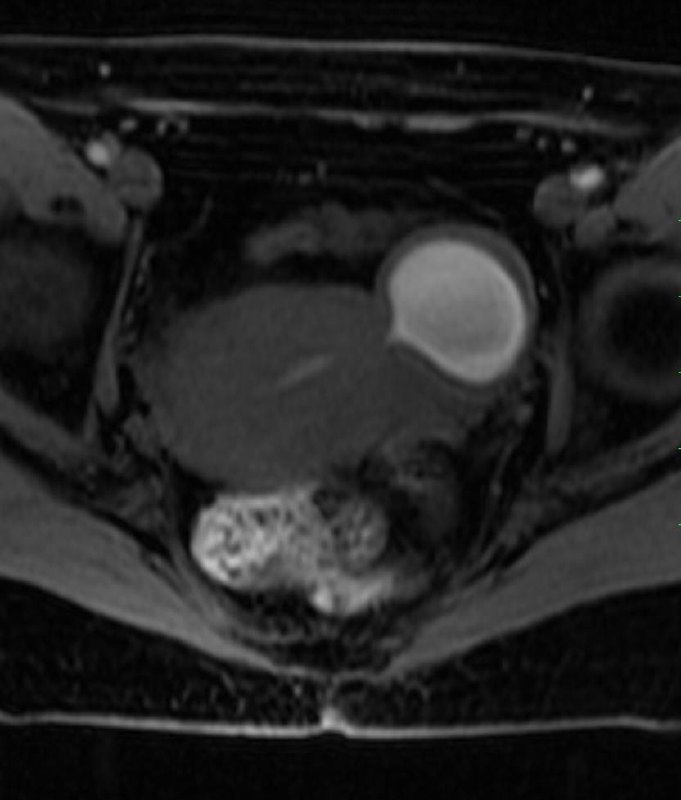

Дивертикул матки у женщины 45 лет.

Дивертикул матки - это редкий врожденный порок развития, вызванный аномальным слиянием мюллеровых протоков.

Диагноз дивертикула матки затруднен, и его часто неправильно диагностируют как другую аномалию Мюллерова протока (например, кровь в рудиментарном роге матки), миому матки с дегенерацией, эндометриому или геморрагическую кисту яичника.

Встречается так редко, что я, вот, первый раз сам увидел, и то, спасибо коллеге из Алма-Аты.